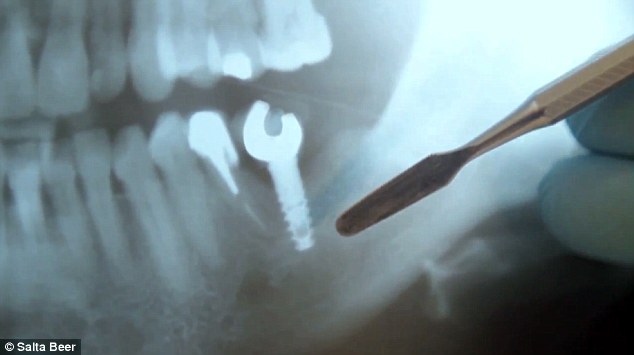

A marca de cerveja argentina Salta, em parceria com a agência Ogilvy & Mather Argentina, criou uma forma de implante dentário que promete ser a solução para quando você estiver sem um abridor de garrafas.

Contudo, embora a ideia pareça ser útil, especialmente para quem sempre pensou abrir uma garrafa com a boca, o implante pode ser perigoso.

De acordo com o Dr. Bruno Puglise, que deu entrevista a um portal de notícias, abrir objetos desta forma pode causar fraturas na coroa do dente e raiz, afetar restaurações e próteses e até mesmo sobrecarregar articulações.